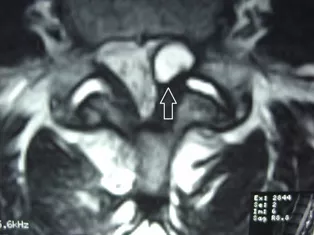

МРТ является методом выбора для диагностики кист межпозвонковых суставов и позволяет в большинстве случаев поставить правильный диагноз.